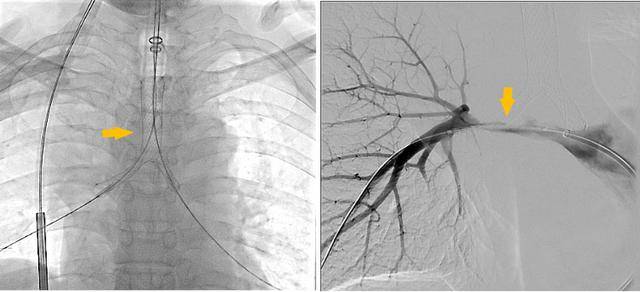

手术过程

潍坊市第二人民医院完成首例气管支架、肺动脉覆膜支架同期植入术

同期置入支架后狭窄明显改善